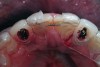

A 19-year-old non-smoking female presented for tooth replacement at the maxillary right and left lateral incisors, which were congenitally missing (Figure 1). The post-orthodontic result was adequate for the placement of 3-mm one-piece small-diameter implants. The preoperative radiographs can be seen in Figure 2 and Figure 3. The pretreatment clinical view in Figure 4 and Figure 5 shows the small intertooth space present in the lateral incisor areas. One of the most challenging tasks with congenitally missing lateral incisor cases is to create an acceptable soft tissue emergence profile from a crestal profile that is flat from the mesial of the canines to the distal of the centrals (Figure 4 and Figure 5). After pretreatment planning which consisted of a complete medical and dental history, radiographic analysis, and upper and lower study models mounted by a facebow transfer technique, the fabrication of a TempStent II surgical guide was completed. Figure 6 and Figure 7 show the occlusal view of the TempStent II guide on the study cast and in the oral cavity, respectively.